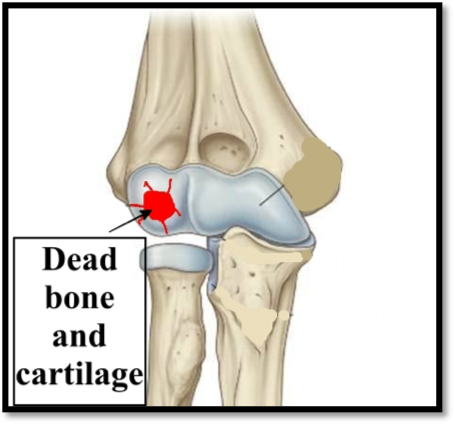

In this condition the blood supply to a small part of the bone with the cartilage on top of it gets interrupted. This part of bone and cartilage becomes dead. In some patients the blood supply gets restored and the lesion heals. This is usually in adolescents and young patients. In older patients the dead bone and cartilage get separated and form loose body in the joint.

There is pain and sometimes swelling in the elbow in the initial stages. There is pain in movements and tenderness at the spot of the lesion. If it heals then pain and swelling decrease slowly.Later when a loose body forms, the elbow joint may get locked in one position. Such locking episodes may occur once or multiple times. These episodes are painful. Other patients may feel clicking inside the joint occasionally.

X-rays, MRI and if a loose body is seen then a CT scan may be required.

It depends on the stage of the disease. If there is a loose piece lying in the joint then the only option is arthroscopic surgery. There are two puncture holes around the elbow joint and the loose piece is extracted. If the defect left behind by the loose piece is small then only a small additional procedure is required. If the defect is large then there are other options that can be discussed with the doctor during consultation.